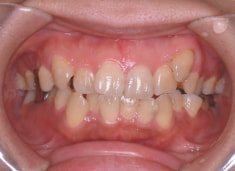

治療開始時